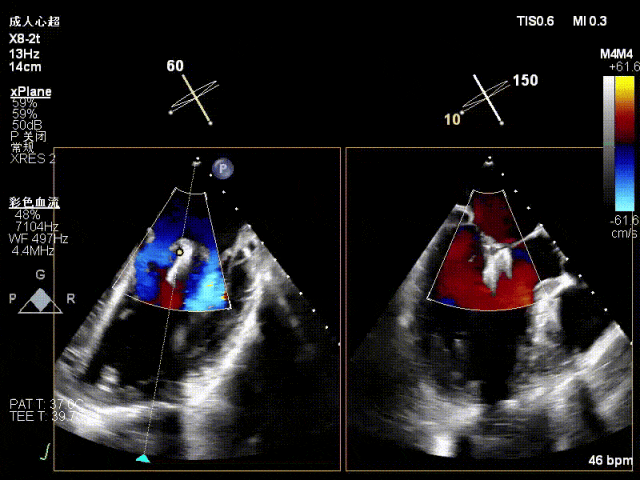

术前术后对比图

术前

术后

术后,出院检查报告显示夹子位置固定,无移位,二尖瓣轻度反流,左室大小和LVEF值正常范围,左室壁运动分析未见明显异常。

术前术后对比图:

术后,出院检查报告显示夹子位置固定,无移位,二尖瓣轻度反流,左室大小和LVEF值正常范围,左室壁运动分析未见明显异常。术后两个月随访检查,状态稳定,夹子位置固定,二尖瓣轻度反流,左室大小和LVEF值正常范围,左室壁运动分析未见明显异常(左室壁运动记分指数1分)。

术后,出院检查报告显示:夹子位置固定,二尖瓣轻度反流,左室稍大,LVEF值正常范围,左室壁运动分析未见明显异常(左室壁运动记分指数1分)

术后,出院检查报告显示夹子位置固定,二尖瓣、三尖瓣及主动脉轻微反流,左房增大,左室内径正常上限,EF值正常下限(WMSI 1分)。